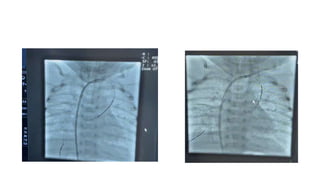

Procedure: Vertical vein stenting under Local

anesthesia

Procedure: Vertical veinstenting under Local anesthesia

Post procedure • Babyshifted to NICU for further management • OG feed started after 2 hours of procedure • Next day echocardiography done. • It showed: Supracardiac TAPVR with vertical vein stents, Moderate size ASD secundum, Dilate RA and RV, mild TR 30 mmHg, LVEF 70% and normal RV function.